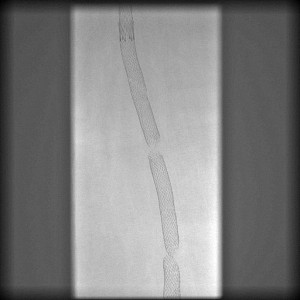

Stent Fracture Types

There are 5 types of stent fractures. Fracture types I-IV describe fracture of one wall of the stent or both and on the number of fracture locations. Type V involves spiraling as well.